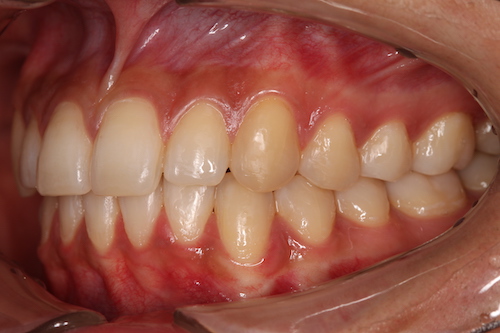

До